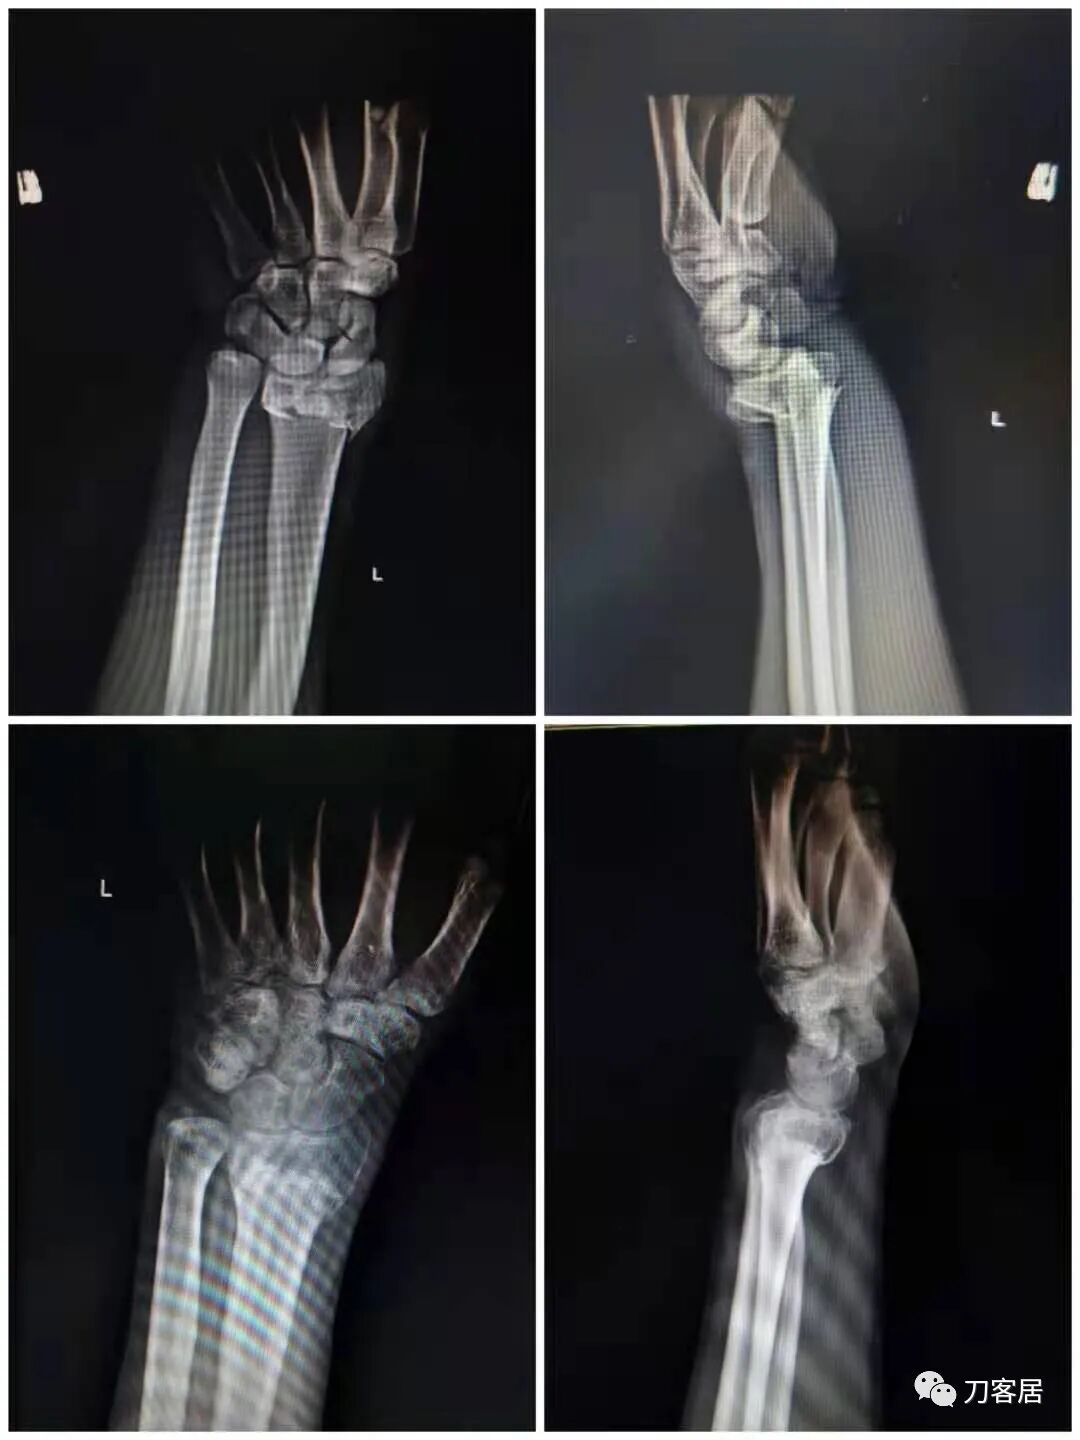

2021年7月22日晚,上海美华医院儿童骨科的师东良医生,给我提供了一例他处理的严重移位尺桡骨双骨折病例,经过手法复位,石膏外固定治愈。这个病例,其他医院建议要做手术。实际上,这样的病例,在现实中有太多太多,因为手法复位,石膏外固定治疗骨折,这是骨科医生的基本功。

下面为师东良医生提供的病例:

超声引导下闭合手法复位石膏外固定治疗7岁患儿尺桡骨远端移位双骨折。

男,7岁,左前臂远端桡尺骨双骨折,术前X光片见图1,行超声引导下闭合复位石膏外固定术,康复训练,6周拆石膏,随访2.5月的效果。术后2.5X光片见图23。功能上仅前臂旋后较健侧减小15°,继续加强康复训练中。家长满意,评价见图4

1. 超声引导下闭合复位石膏外固定术左尺桡骨双骨折

2. 超声引导下闭合复位石膏外固定术后2.5月左前臂正位X光片

3. 超声引导下闭合复位石膏外固定术后2.5月左前臂侧位X光片